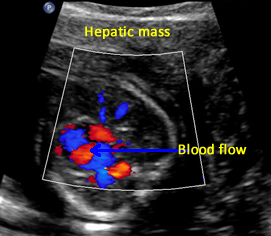

Above. Gestational age is 22 weeks. Potential hepatic tumor of mixed echogenicity.

Above. Gestational age is 22 weeks. Potential hepatic tumor of mixed echogenicity. Color Doppler demonstrates blood flow to the heterogeneous mass. The differential diagnosis includes hemangioma or one of its varieties or hepatoblastoma.